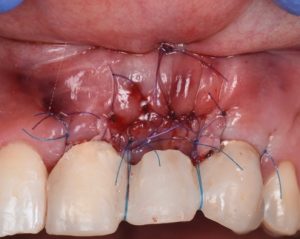

This video presents Part 2 of a staged pontic site development protocol, performed five months after the initial soft tissue augmentation. The objective of this second surgery is to further enhance soft tissue volume and achieve root coverage in preparation for a future fixed partial denture (FPD).

The procedure demonstrates the use of a horizontal vestibular incision with tunneling to mobilize the soft tissues and elevate the papillae. An autogenous connective tissue graft (CTG) harvested from the palate and maxillary tuberosity is utilized to augment tissue thickness. Additionally, a xenogenic bone graft is placed over the crestal area to serve as a space-maintaining scaffold and support vertical tissue stability.

Advanced flap advancement and suturing techniques are highlighted to ensure graft stability and optimal soft tissue outcomes.